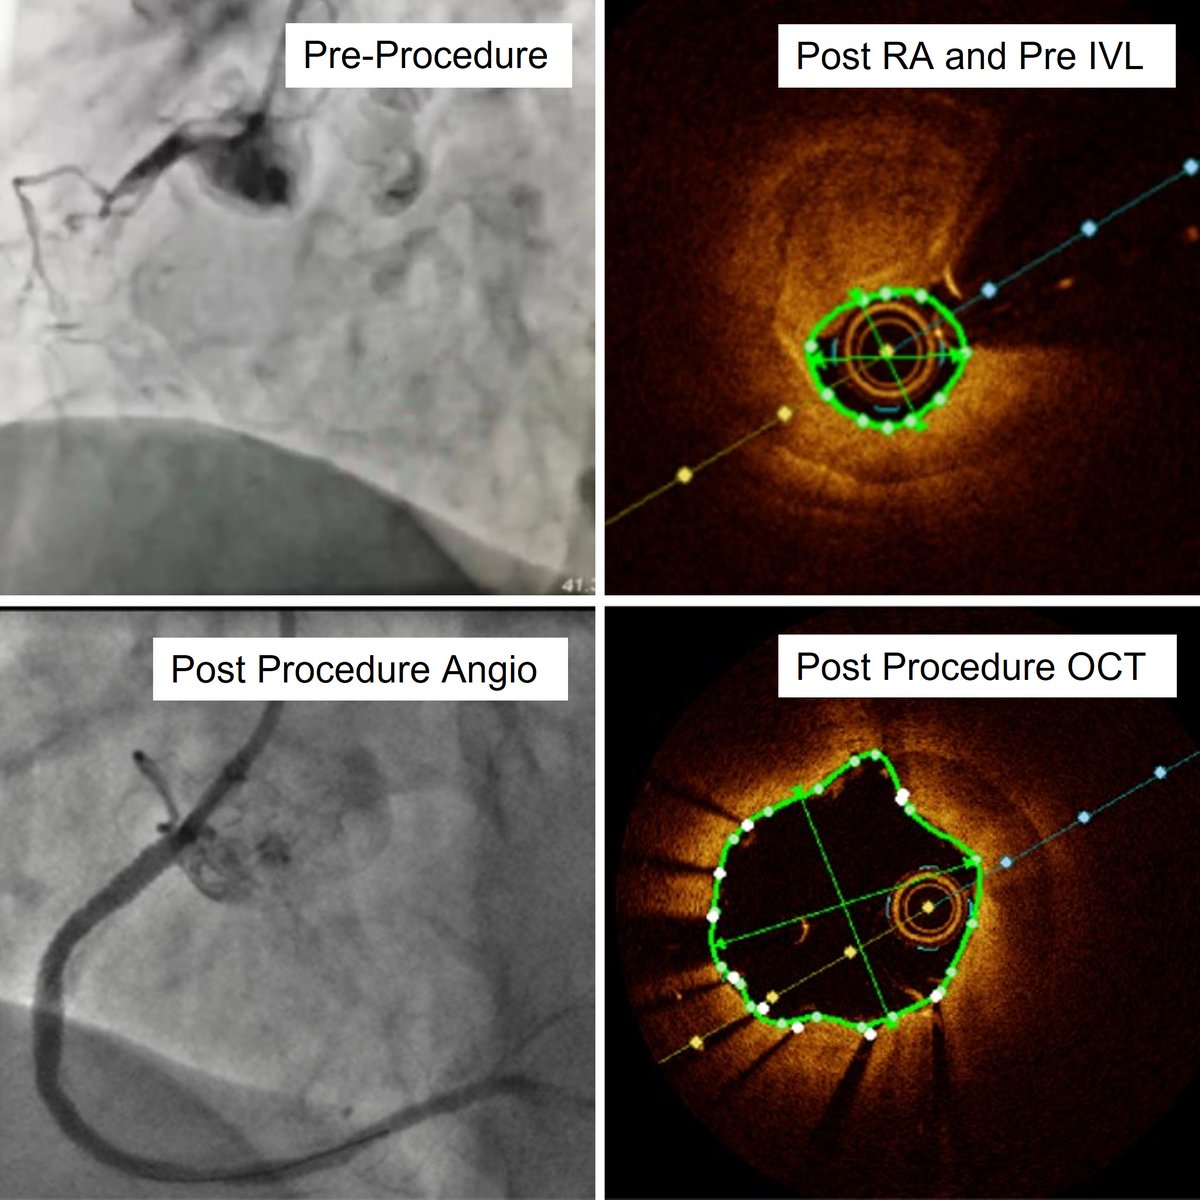

Check out the before and after images of this HD #IVUS guided #RotaShock PCI to optimize deployment of a 3.00x38mm SYNERGY XD. Congrats to @DoctorMoussa of @VirtuaHealth on successfully opening this heavily calcified LAD, making for a great #ComplexPCI case!

BSCCardiology's tweet image. Check out the before and after images of this HD #IVUS guided #RotaShock PCI to optimize deployment of a 3.00x38mm SYNERGY XD. Congrats to @DoctorMoussa of @VirtuaHealth on successfully opening this heavily calcified LAD, making for a great #ComplexPCI case!